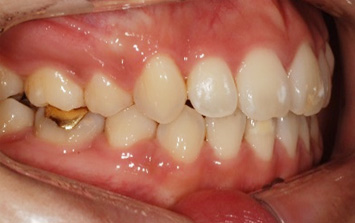

앞니가 정상적으로 물이지 않아 심미적인 문제와 음식물을 섭취할 때 상당한 불편함을 느껴 내원한 환자.

고운미소에서는 교정용 와이어와 미니스크류를 사용하여 치열의 수직적인 문제를 개선하는 치아교정을 시행하였습니다.

앞니가 서로 물리게 되어 음식물을 씹는 저작 문제와 심미적인 문제가 해결되어 교정을 완료하였습니다.